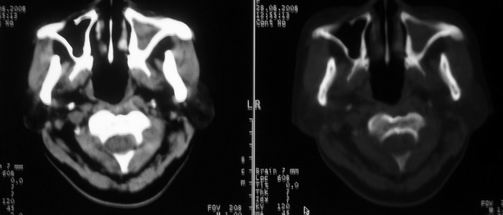

女,55岁,右侧颌下肿物3年。

鼻咽左侧壁增厚,呈结节样突入鼻咽腔内,左侧咽隐窝消失,须考虑鼻咽癌可能,建议鼻咽纤维镜检查以明确诊断。

至于右侧颌下间隙的结节影,如果不考虑病史的话,可以诊断为淋巴结转移。但是结合病史“右侧颌下肿物3年”,又不象淋巴结转移了。建议ct增强扫描明确结节与右侧颌下腺的关系,或者穿刺活检定性。

右侧胸锁乳突肌内侧略低密度结节,应该是静内静脉而不是淋巴结。